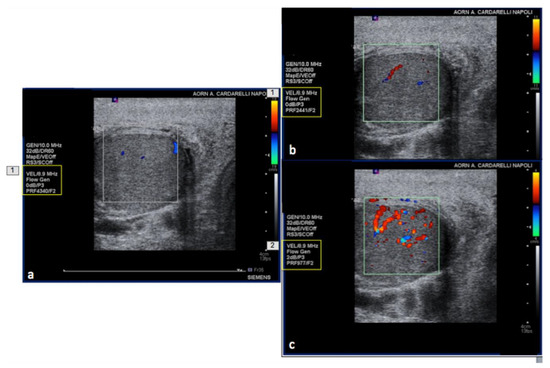

Figure 15. PRF setting. High- (a) middle- (b) and low- (c) PRF setting show progressive better evidence of intra-testicular flow at low setting (yellow box).